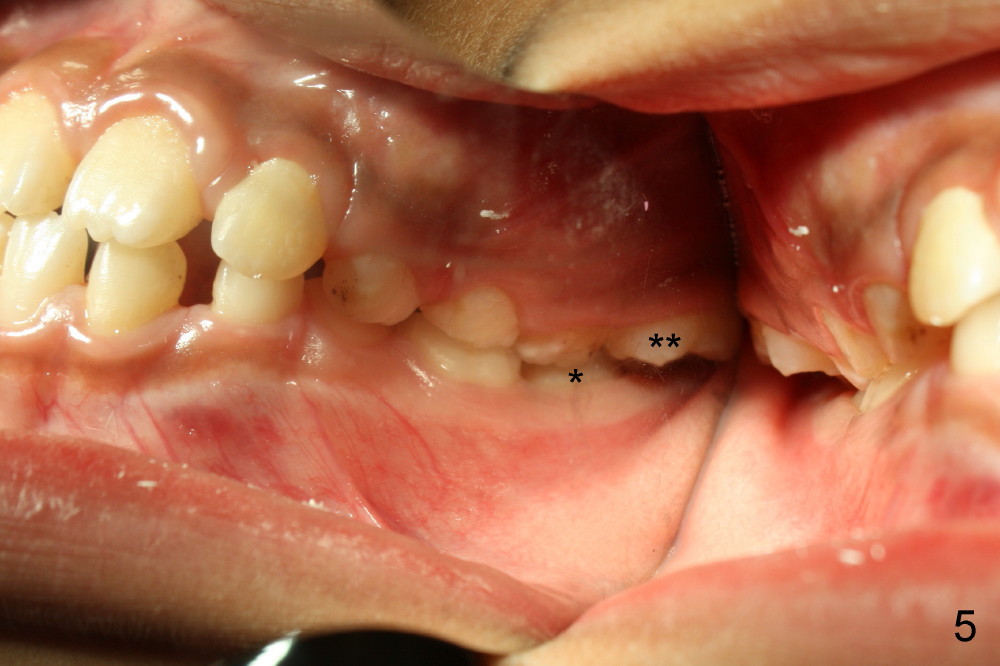

It appears that the chin deviates to the left (Fig.1). The lower dental midline also deviates (Fig.2,4). Profile shows possible bimaxillary protrusion (Fig.3). There is cross bite (deep overjet?) on the right side of the first permanent molars (Fig.5 mirror image), whereas the left posteriors apparently present edge-to-edge occlusion (Fig.6). Fig.7,8 are mirror views of the upper and lower arches, respectively. Panoramic X-ray demonstrates elongation of the right condyle (Fig.9). The right ramus appears to be longer than the left.